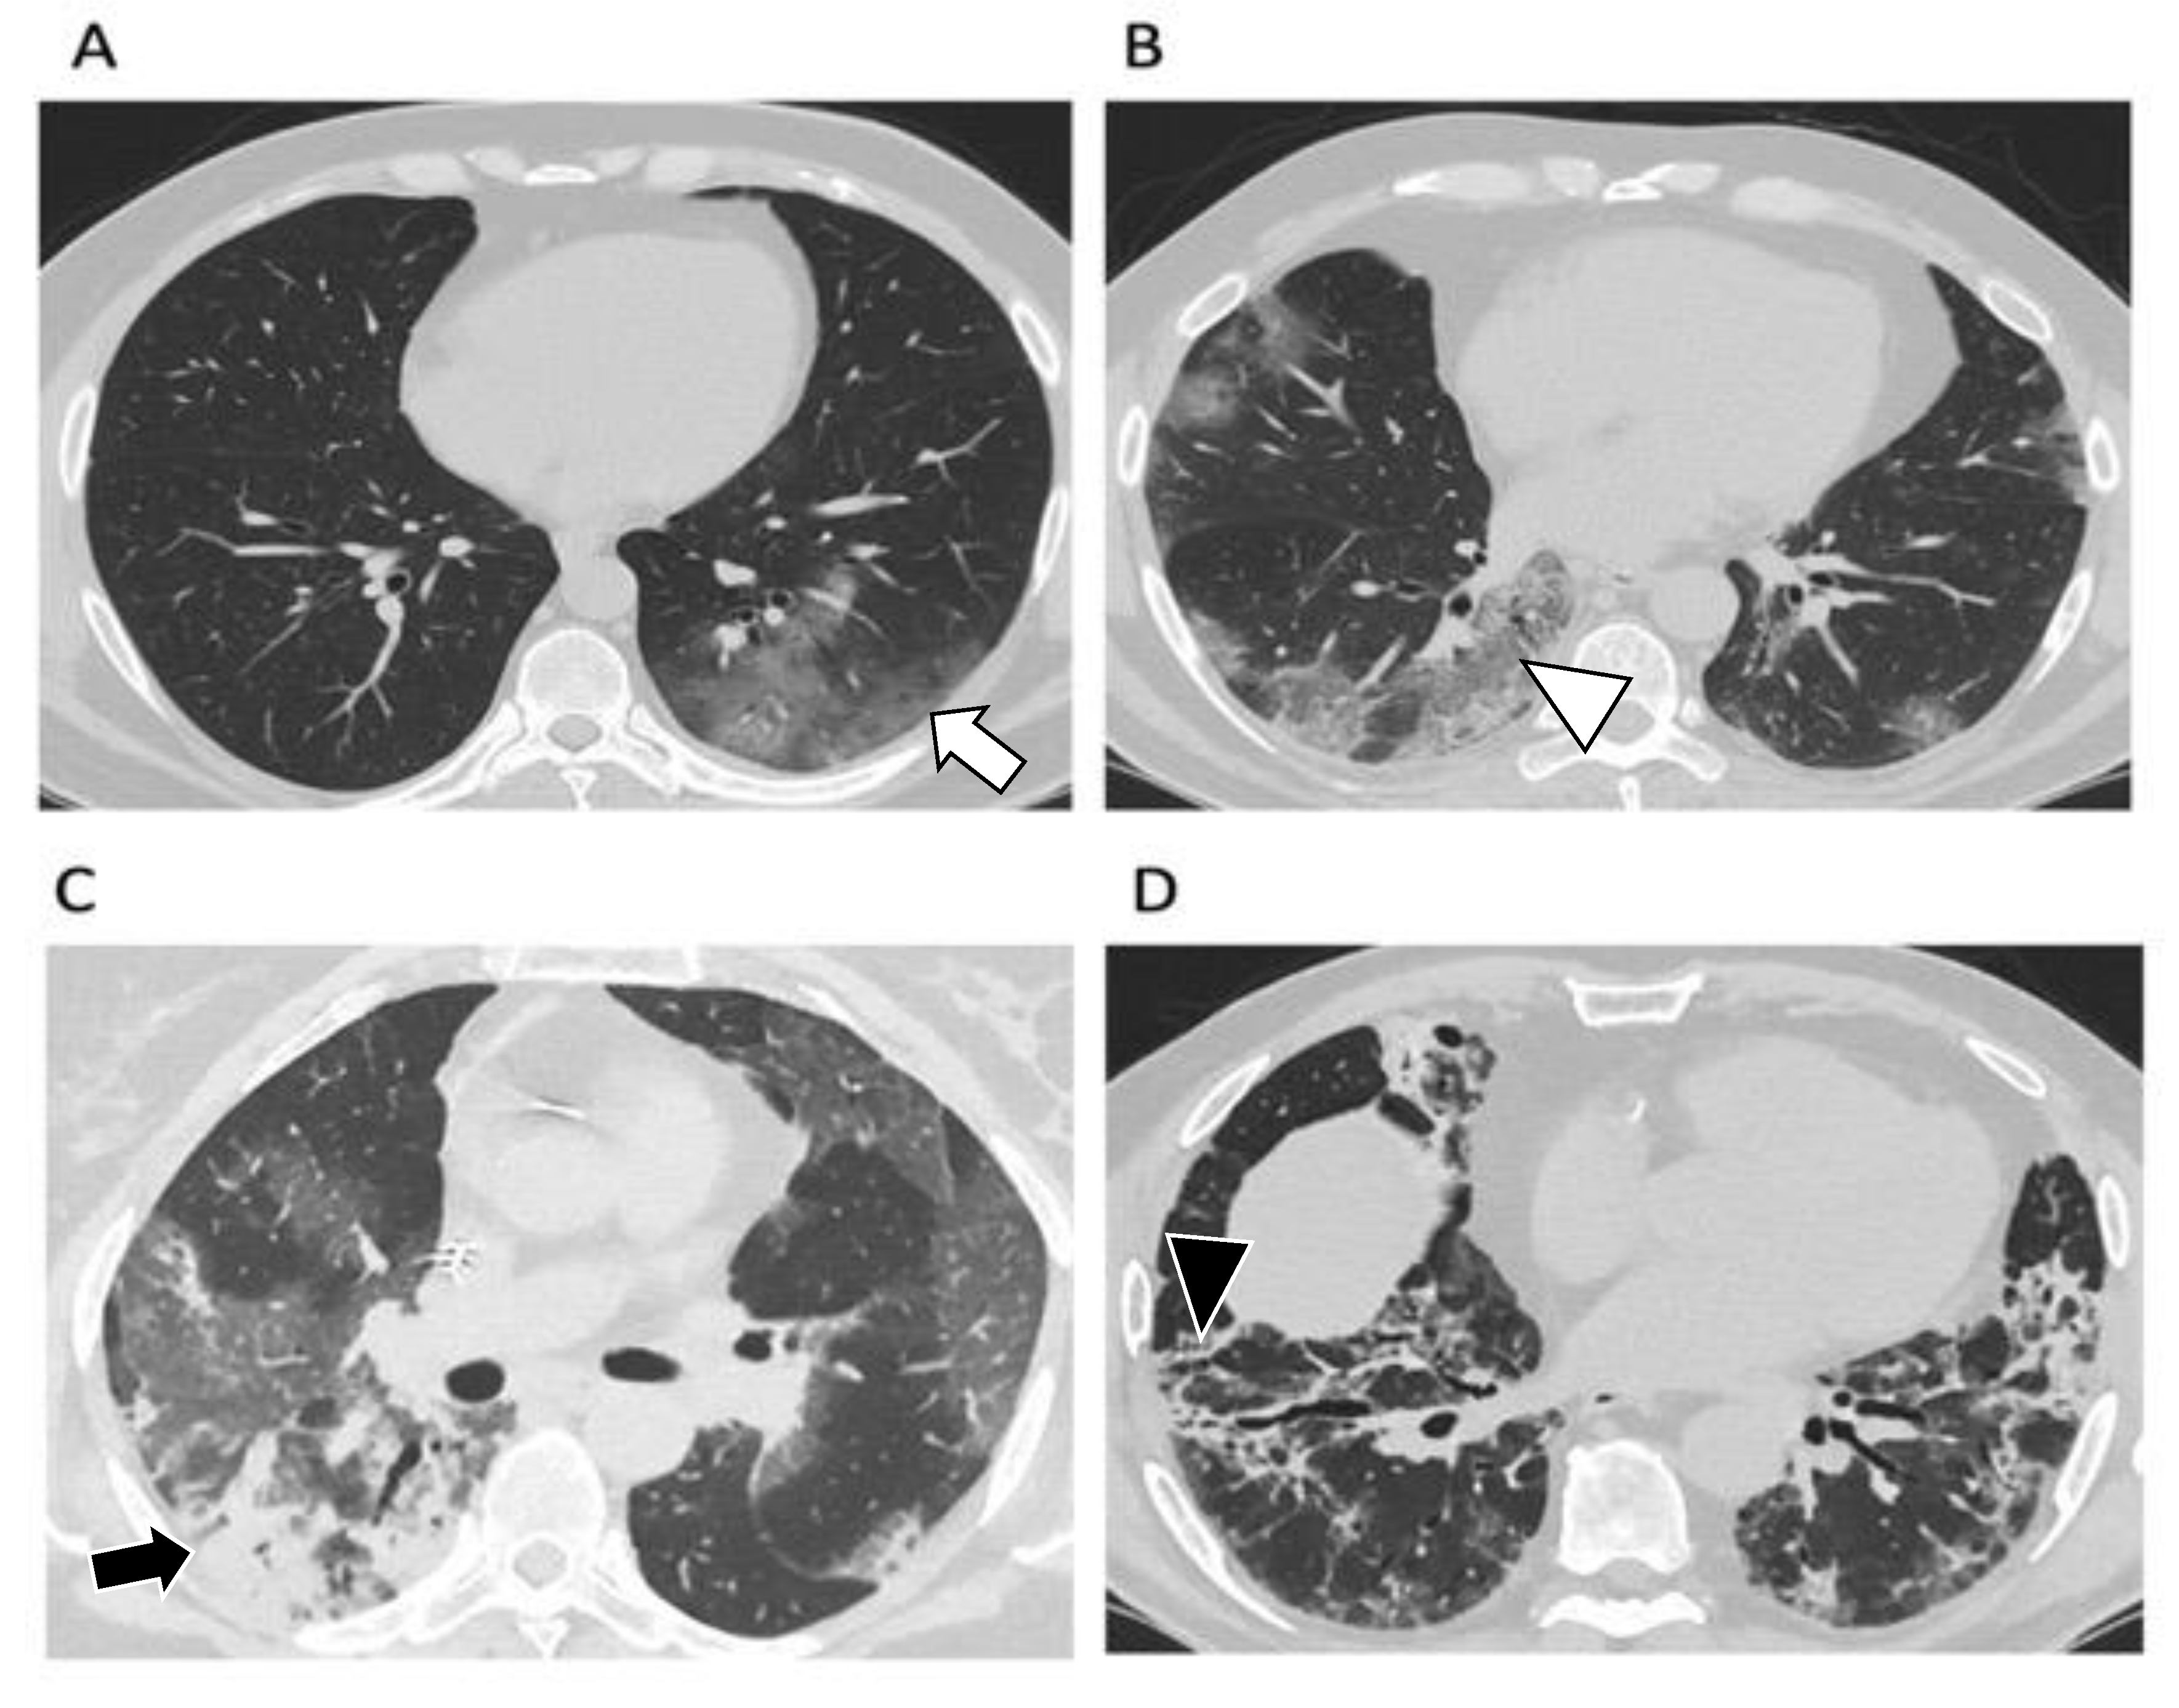

2.2. Typical CT Findings

2.3. CT Findings Evolution

2.4. Disease Severity

2.5. Complications